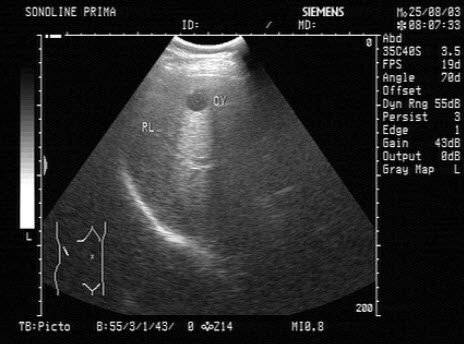

27、单项选择题

女性,56岁,消瘦、腹部膨隆3月余。妇科检查:盆腔触及包块。超声检查如图,最可能的诊断为()

A.转移性卵巢癌

B.囊腺癌

C.黄体囊肿

D.黄素囊肿

E.囊腺瘤